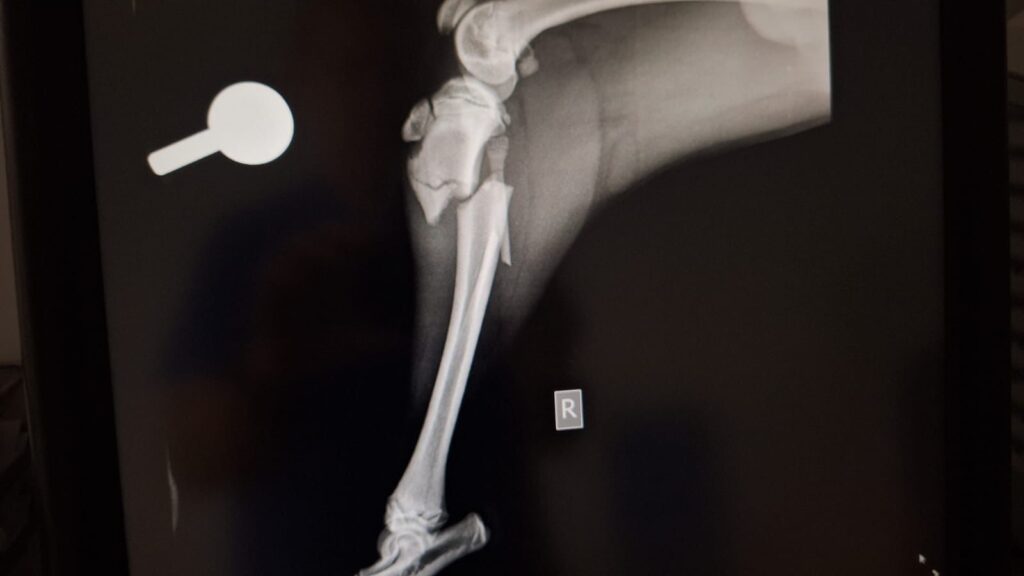

Kaiser braucht eure Hilfe

Kaiser wurde in Spanien überfahren und hat massive Verletzungen an 3 Beinen erlitten. Er wurde operiert und hat sich inzwischen auch schon recht gut erholt. Kaiser ist erst 9 Monate und ein sehr lieber und geduldiger Junge.